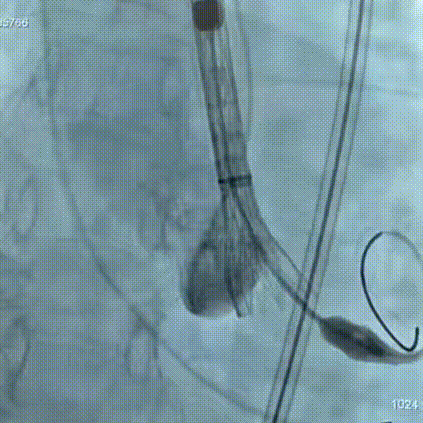

手术过程:在右股动脉穿刺建立通路后,顺利送入大鞘,经食道超声及血管造影确认路径稳定。18mm球囊预扩后评估冠脉灌注良好,后将Prostyle A® AV26瓣膜精准释放于目标位置,超声显示无瓣周漏,术后即刻造影显示无明显反流,术前PGmean40mmHg,术后导管测平均跨瓣压差8mmHg,心功能明显改善,患者生命体征平稳。

最终造影形态位置良好,无瓣周漏